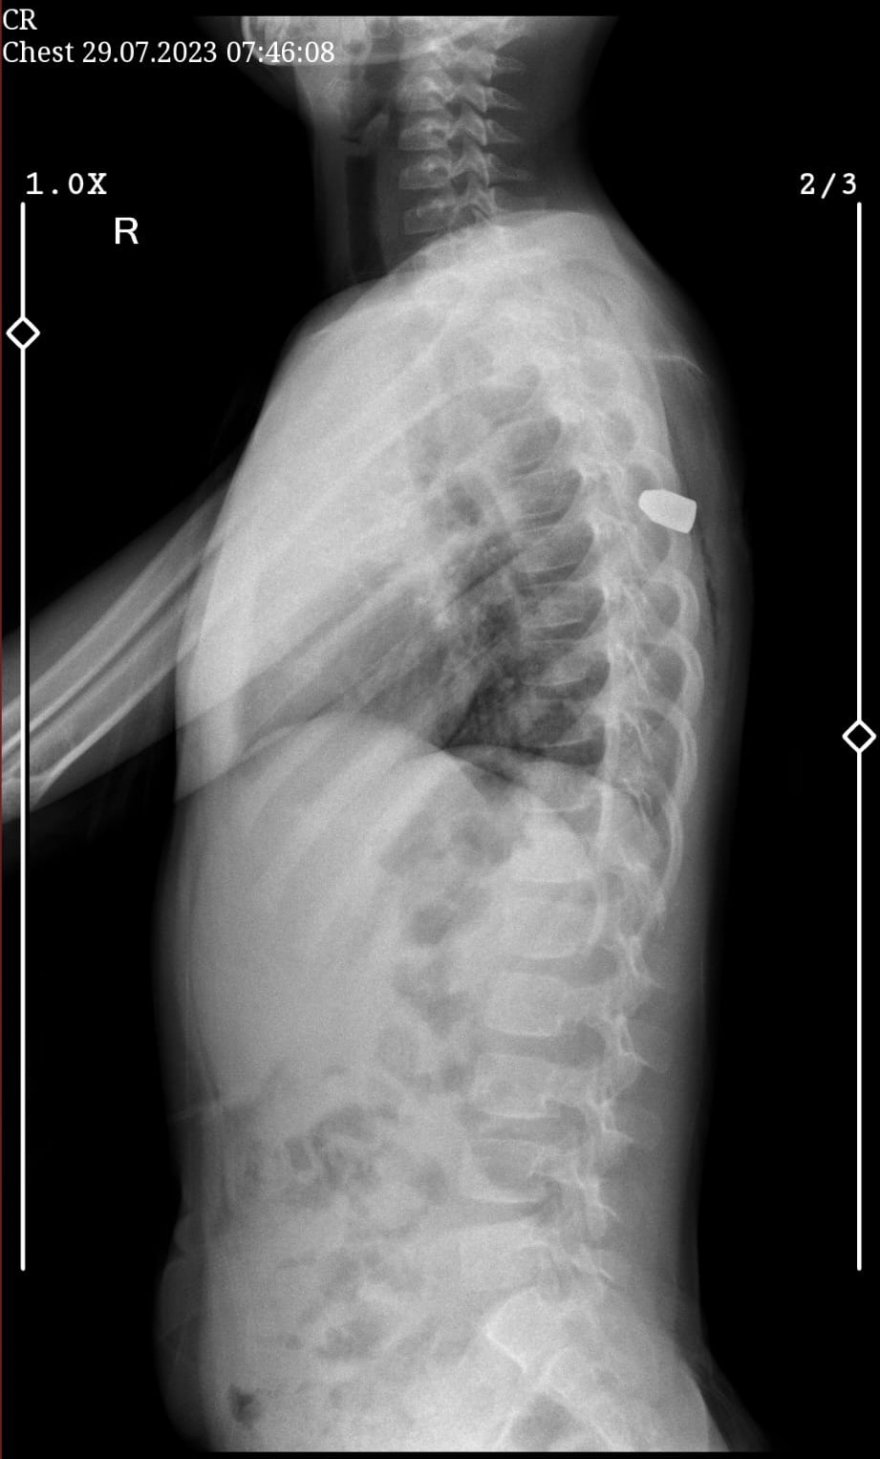

Aile kızlarını Adana Şehir Eğitim ve Araştırma Hastanesi'ne götürdü. Burada çekilen ultrasonda Meliha'nın sırtına yorgun mermi isabet ettiği tespit edildi. Hemen ameliyata alınan ve hayati tehlikeyi atlatan Meliha'nın hastanede tedavisi sürüyor.